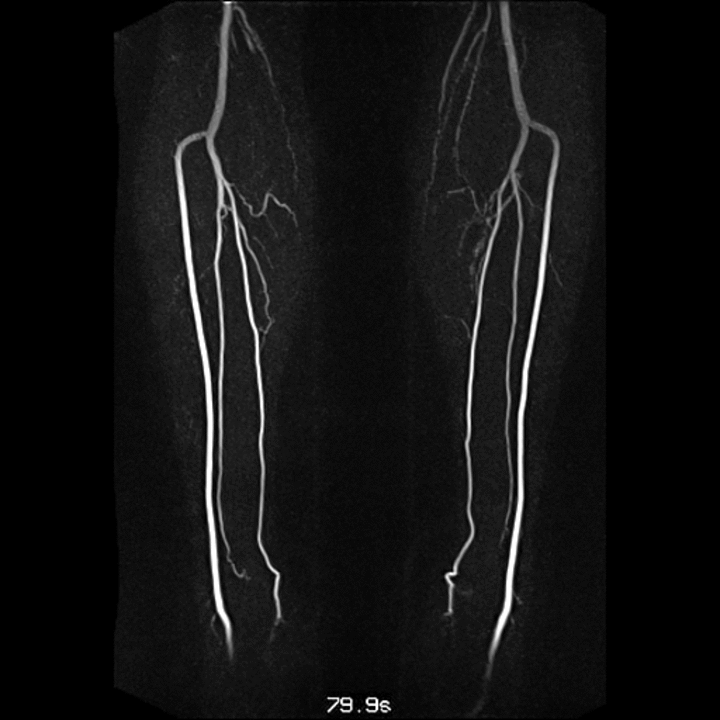

Arteriogram

An arteriogram is an X-ray of the blood vessels called arteries. It is performed to evaluate various vascular conditions, such as an aneurysm (a bulging, weakened area in the wall of a blood vessel), stenosis (narrowing of a blood vessel), or blockages. Other names for this procedure are angiogram and arteriography.